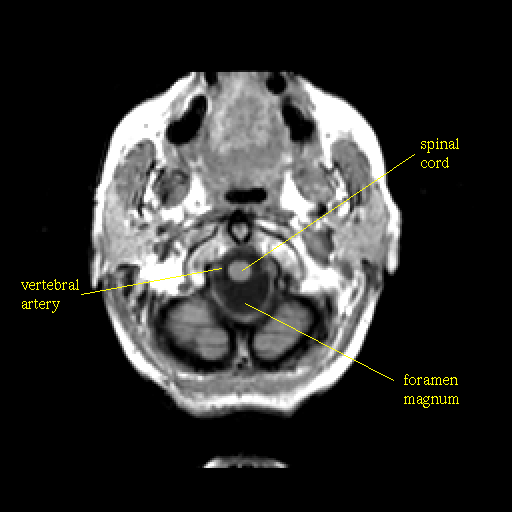

T1-weighted structural MR: Slice 4

Slice 4